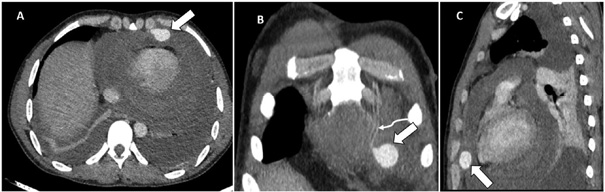

The patient was quickly transferred to the radiology department for a CECT of the chest. During the transfer, he received one unit of whole blood. The CECT showed a contrast-filled outpouching from the left IMA. It measured about 1.5 × 2.1 × 2.2 cm (anteroposterior × transverse × craniocaudal). This was consistent with a pseudoaneurysm. In addition, there was hemopericardium, and hemothorax. No active contrast extravasation or pulmonary parenchymal injury was noted (Figure 1).